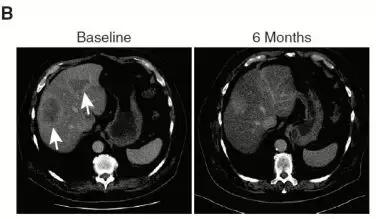

(一)患者检测到MET扩增(12个拷贝数),使用克唑 替尼后,肝转移消失,疾病控制达到5个月。

(二)胃癌患者检测到FGFR2扩增,患者对FGFR2*制剂抑**AZD4547有效,治疗6个月后,肝转移灶基本消失。